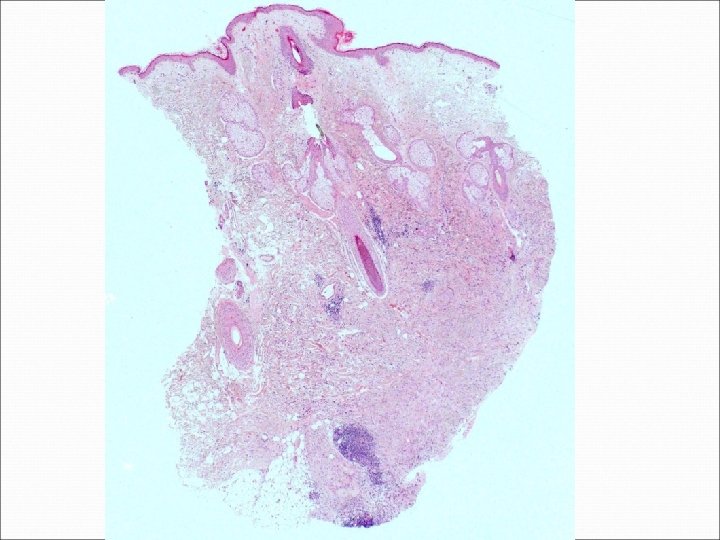

National Specialist Dermatopathology EQA Scheme Circulation L